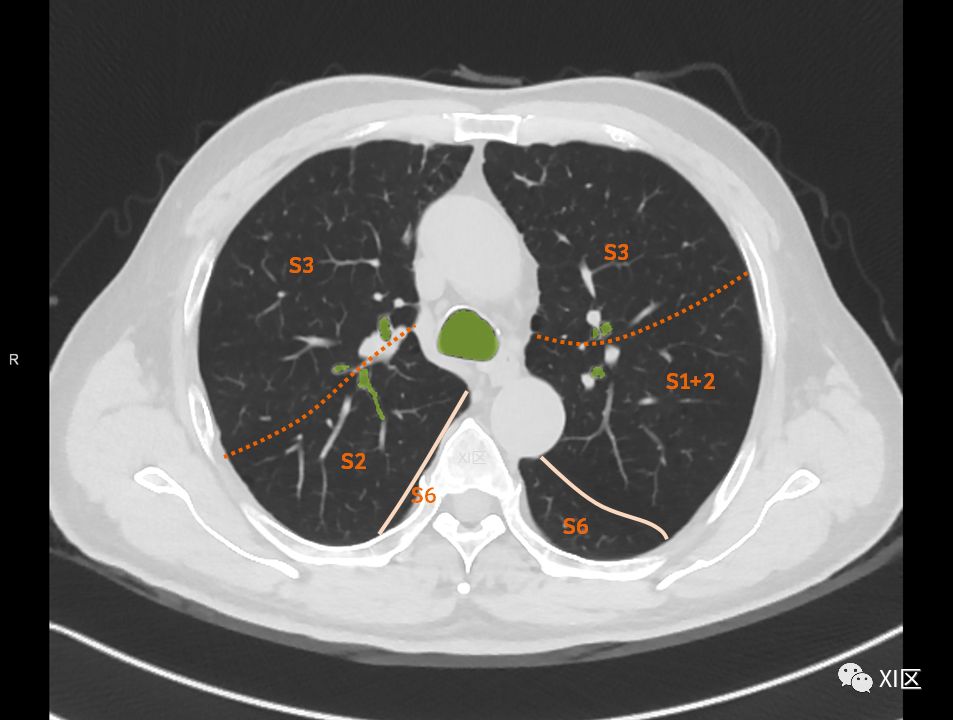

肺的断层分段示意图

在进行肺的分段时,可以上下观察浏览,沿着相应气管的走形可以更容易准确地进行分段。